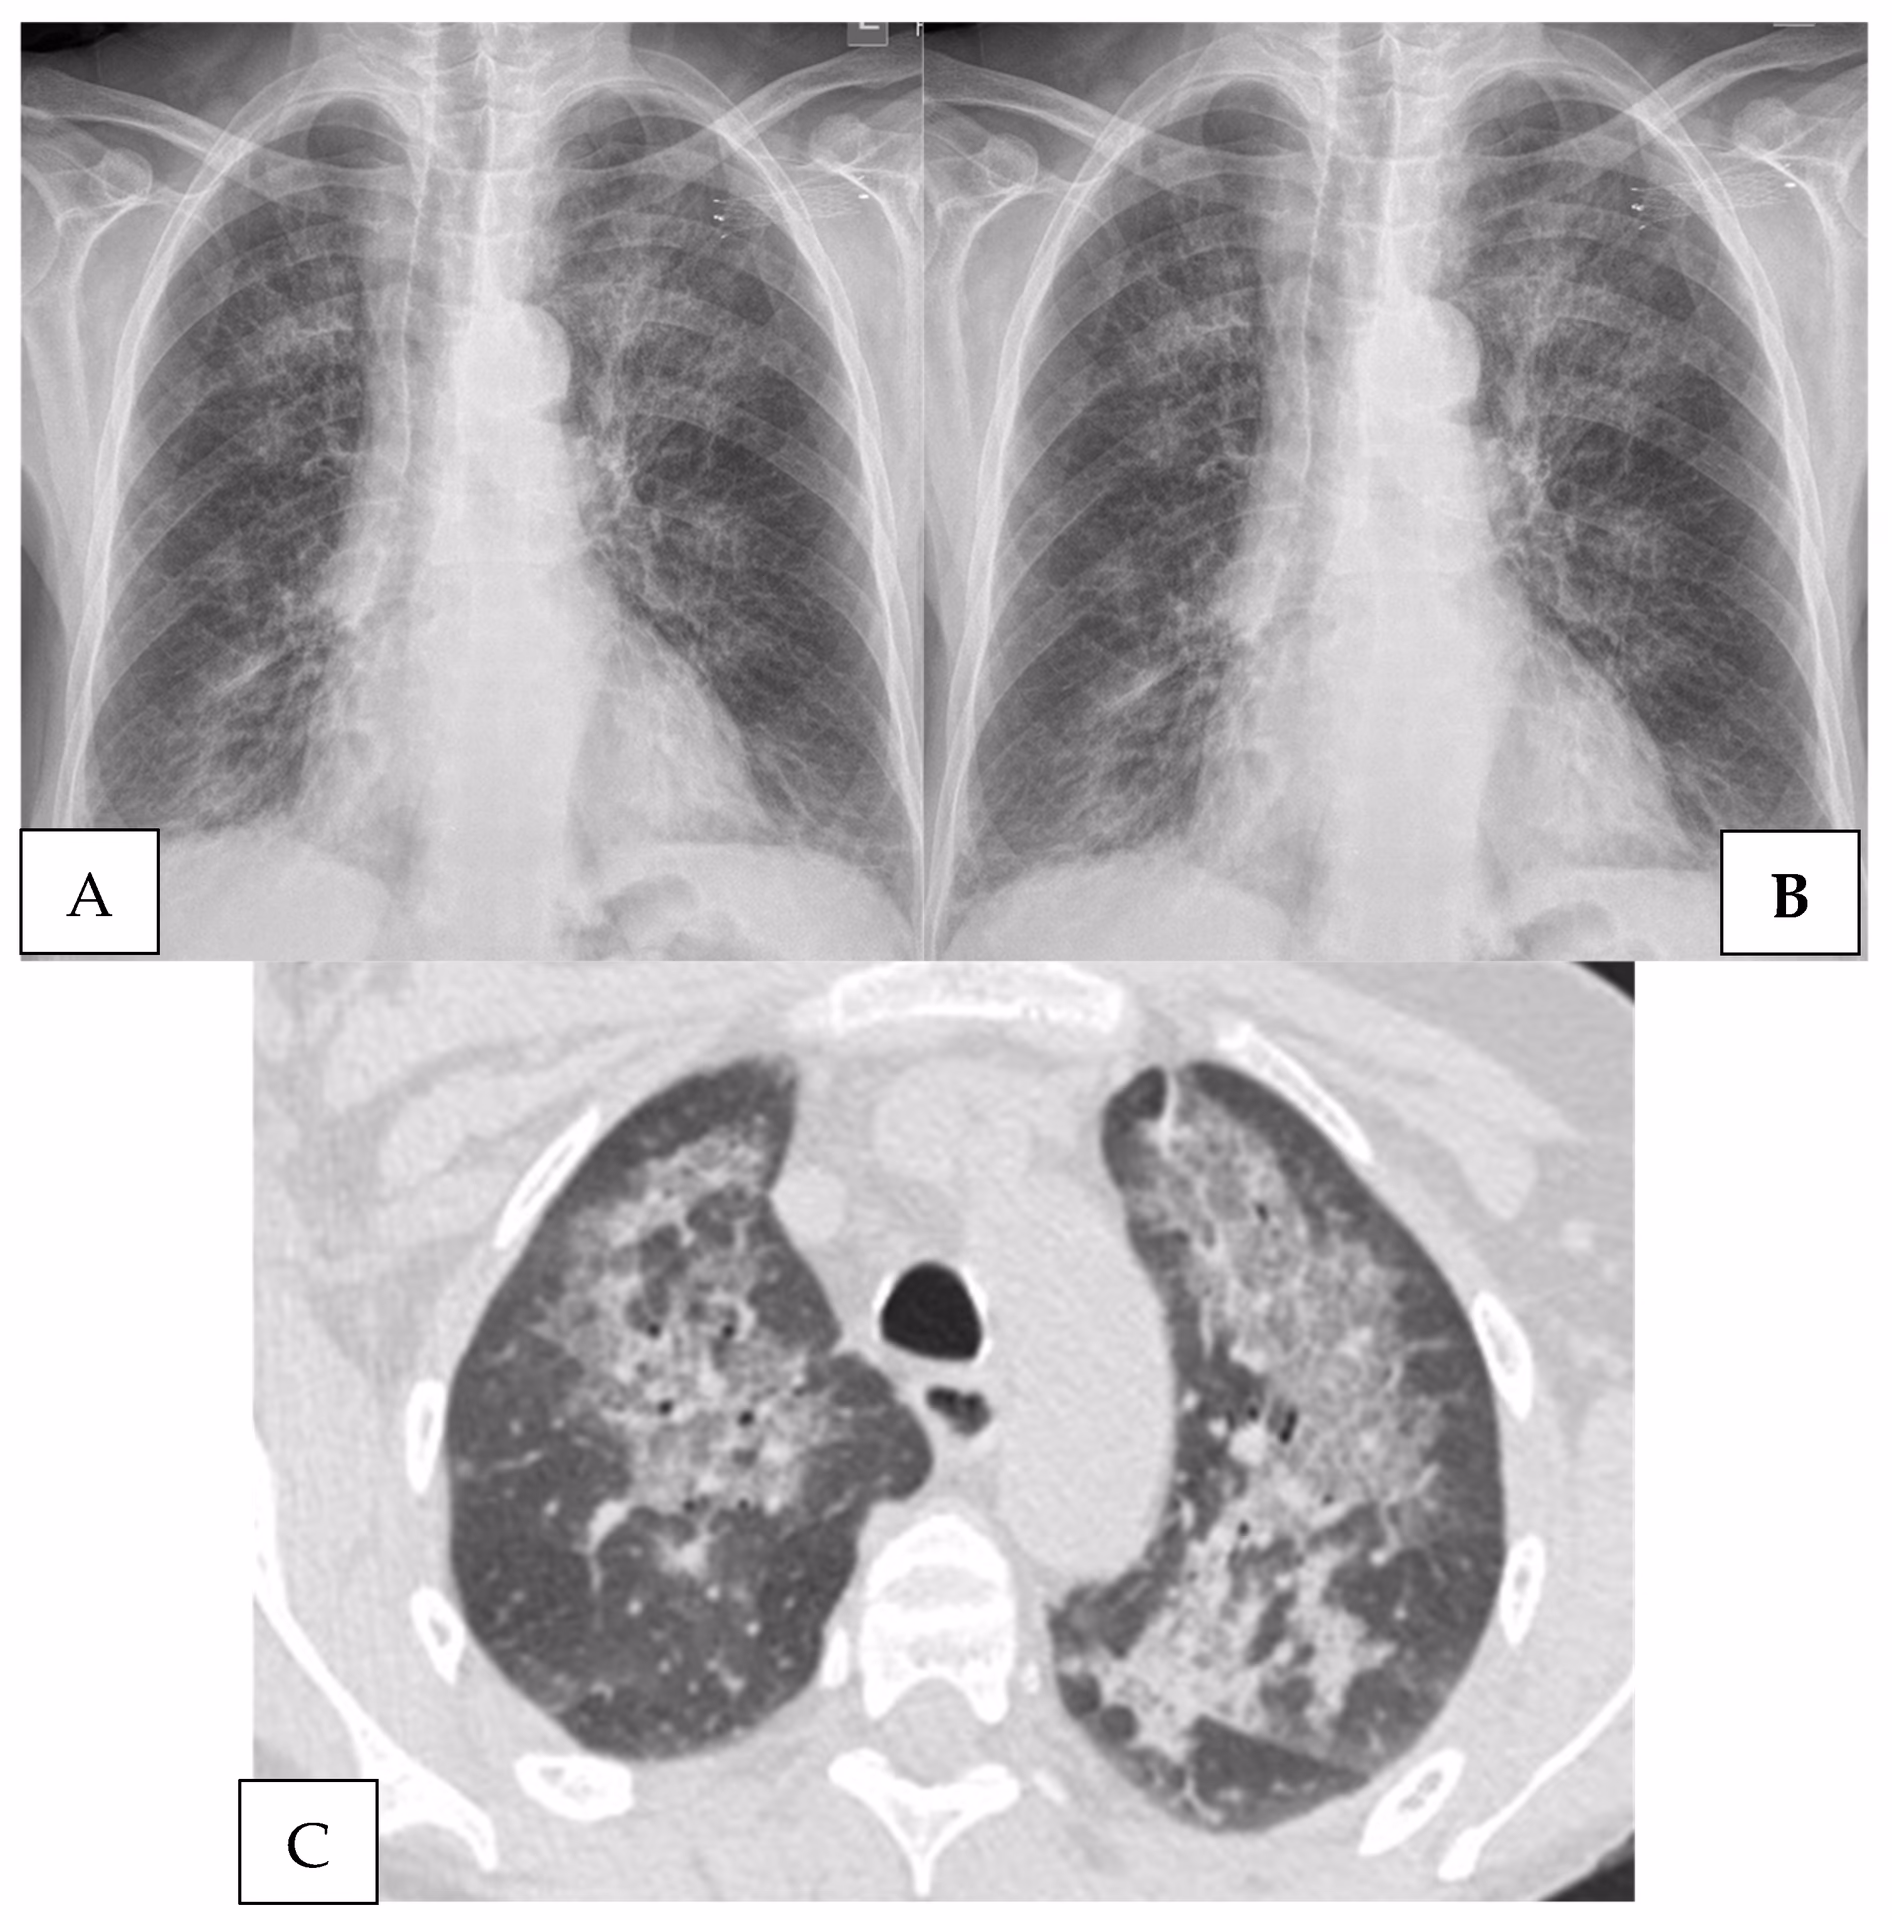

Billeddiagnostik

Røntgen af thorax (brystkasse): Det klassiske fund er diffuse, fine, retikulære (net-lignende) infiltrater, der spreder sig fra lungehilus (området hvor luftrør og store blodkar går ind i lungen) og ud i begge lunger. Det er dog vigtigt at vide, at op mod 10-15% af patienter med PJP kan have et helt normalt røntgenbillede i starten af forløbet.

CT-scanning af thorax: En højopløselig CT-scanning (HRCT) er langt mere følsom end et almindeligt røntgenbillede. Det mest karakteristiske fund er udbredte, diffuse områder med ”matglas-fortætning” (ground-glass opacities), som indikerer væske eller betændelse i lungeblærerne. Der kan også ses små luftfyldte cyster (pneumatoceler), især i de øvre dele af lungerne.